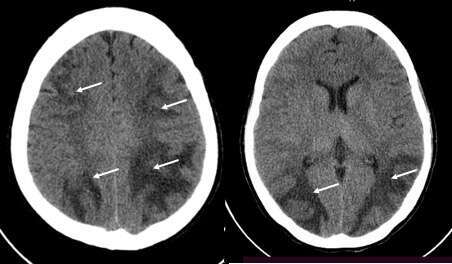

We present a 24-year-old G1P1 (1001) postpartum Day 11, who was admitted for seizures. On her 10th postpartum day, the patient suddenly developed severe occipital headache, nape pain, and diplopia. Within 6 hours, she experienced a 1-minute generalized tonic-clonic seizure and loss of consciousness. At the ER, her blood pressure was 190/110 mm Hg while the rest of her vital signs were within normal limits. A second episode of tonic-clonic seizure associated with diplopia and loss of consciousness resolved after administering diazepam 5mg intravenously. Initial evaluation showed eclampsia, diplopia and proteinuria. Magnesium sulfate infusion was given. An electroencephalogram obtained 24 hours post-ictal was normal. Unenhanced cranial computerized tomographic (CT), which was performed on Day 2 post-ictal, showed confluent, fairly symmetrical, bilateral white matter hypodensities involving the white matter of the bilateral frontal, parietal, and occipital lobes consistent with PRES (Figure 1). No evidence of intracranial lesions nor infarct was appreciated.

All neurological symptoms resolved within three days once the blood pressure was controlled. A follow-up unenhanced CT scan was performed on Day 39 post-ictal, and showed non-delineation of the previously reported bilateral parietal and occipital lobe white matter hypodensities.

Figure 1. Unenhanced cranial CT 48 hours post-ictal show confluent, symmetrical, bilateral white matter hypodensities involving the bilateral frontal, parietal, and occipital lobes (arrows).